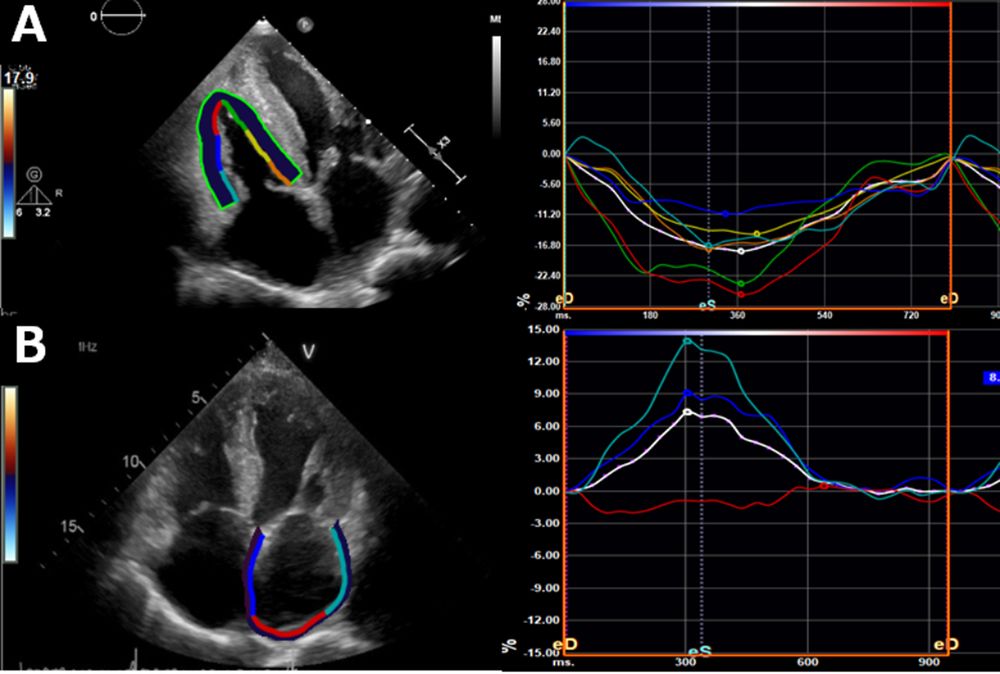

🫀 Breaking: RV function recovery in transthyretin amyloidosis post-tafamidis at #IJCVI.

🌐

Recovery of right ventricular function in patients with transthyretin cardiac amyloidosis after one-year tafamidis administration

The International Journal of Cardiovascular Imaging - Baseline cardiac functions are known to be potent predictors of cardiovascular events in the natural history of transthyretin amyloid...

doi.org